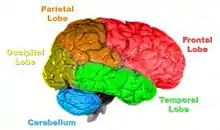

Brain-damaged patients have provided useful insights into the underlying biological mechanisms involved in false recognition. Results from studies comparing levels of false recognition between patients with frontal lobe damage and age-matched controls, showed a significantly higher level of false recognition amongst the frontal lobe damaged individuals.[2] The damage is believed to have caused disruptions in the adequate encoding of item-specific details or caused defective retrieval monitoring processes. These types of processes are needed to accurately recall the origins of memory representations, and without them, errors of origin can be made. Studies of false recognition in amnesic patients with damage to either the medial temporal lobe or other diencephalon structures, have demonstrated that the same processes involved in accurate recognition, are also involved in false recognition.[2] These cortices play a role in strategic monitoring processing, as they attempt to examine other cortical outputs. If these cortices were damaged, there would be no control over the cortical outputs, increasingly the likelihood of a false recognition error. Additionally, patients with amnesia or Alzheimer's disease have a reduced level of false recognition, believed to be caused by taking too many trials to create the semantic gist information needed for the attribution error.[2]

A follow-up to the previous research was conducted by Daniel L. Schacter and colleagues. Similar to the study by Henry L. Roediger and Kathleen McDermott, subjects were read a list of associated words before they went into the PET scanner. During the first scan, subjects would make recognition judgments to determine what were the previous presented words.[2] During the second scan, subjects had to make judgments about words that were not presented. For example: bed, rest, dream, tired, and awake would be in the list but not the word "sleep". As with the study by Henry L. Roediger and Kathleen McDermott, subjects claimed to remember similar amounts of non-presented words as they did the words that were actually presented.[2] The researchers noted that brain activity during the true and false recognition tasks were very similar. Monitoring the blood flow in the brain revealed there were in the left medial temporal lobe for both veridical and illusory recognition.[17]

That is not to say that there were not differences. While monitoring blood flow in the brain during false recognition, a part of the frontal lobe that is thought to be a key monitor of memories actually showed greater activity when presented with a false recognition than with a true one.[2] There seemed to be some discrepancy as subjects attempted to scrutinize the out-placed words, but were overcome by powerful memory illusion.[2] This study demonstrates the ability of technology to help researchers understand to a greater extent the power of false memories.

The researchers found that perirhinal cortex activation was greater for objects recalled, and parahippocampal cortex activation was greater when scenes were recalled.[18] The results provide evidence of distinct encoding activation in the subregions of the medial temporal lobe.[18] The first subregion is the perirhinal cortex, which encodes item information. The second subregion, the parahippocampal cortex, is involved in source information. The evidence provides support for the role of the right perirhinal cortex in attributing an object to the right source.[18] As decreased activation was associated with poorer performance, decreased activation of the right perirhinal cortex could be a possible mechanism for source confusion.